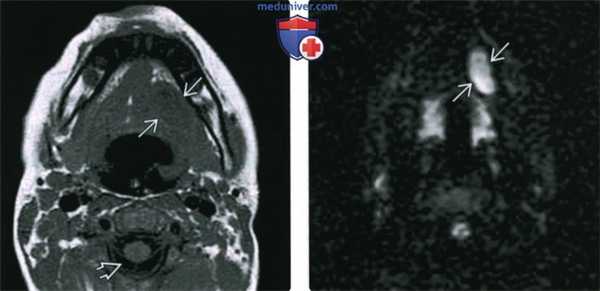

3. МРТ дермоида и эпидермоида полости рта:

• Т1 ВИ:

о Эпидермоид: объемное образование с четкими контурами и однородным жидкостным сигналом:

- Диффузное ↑ сигнала при высоком содержании белка в жидкости

о Дермоид: объемное образование с четкими контурами и комплексным жидкостным сигналом:

- При наличии жира: фокальное или диффузное t сигнала

• Т2 ВИ:

о Эпидермоид: однородный сигнал высокой интенсивности

о Дермоид: неоднородный сигнал высокой интенсивности:

- Промежуточный сигнал при наличии жира

- Фокальные гиподенсные участки (кальцинаты)

• ДВИ:

о Дермоидные и эпидермоидные кисты ± ограничение диффузии

• Т1 ВИ С+:

о Контрастирование в виде тонкого «ободка» либо отсутствие контрастирования

о Снижение интенсивности сигнала в жировом компоненте дермоида при жироподавлении

(Слева) МРТ Т1ВИ, аксиальная проекция. Эпидермоидная киста подъязычного пространства. Сигнал от образования минимально гипоинтенсивный относительно скелетных мышц, выраженно гиперинтенсивный относительно ликвора. Такая картина говорит о повышенном содержании белка, что может свидетельствовать в пользу инфицирования или, вероятно, кровоизлияния.

(Справа) MPT DWI, аксиальная проекция, тот же пациент. Гиперинтенсивный сигнал говорящий об ограничении диффузии. Такой вид может быть характерен и для эпидермоидной, и для дермоидной кисты.